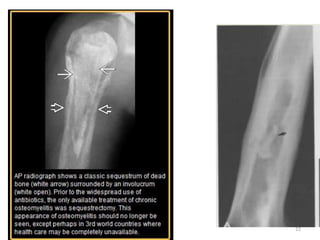

• A sequestrum:

– represents a segment of necrotic bone that is

separated from living bone by granulation tissue.

– Sequestra- nidus for infection.

– As sequestra are devitalized, they remain denser than

surrounding vital bone which become demineralized

due to hyperemia and immobilization.

• An involucrum:

– denotes a layer of living bone that has formed about

the dead bone.

• Cloaca-an opening in an involucrum which allows

drainage of purulent and necrotic material out of the

dead bone.

Bone Changes:

• Bony changes –

- 10-14 days required

– Local osteopenia (at the site of infection,

usually metaphysis) is the earliest bony

change.

– Periosteal reaction follows

– An involucrum is usually visualized after 3

weeks

– Sequestrum is seen as dense, irregular bone

surrounded by lucency (representing

granulation tissue).

– Cloacae (fistula tract) are seen as lucent

areas which are created by external

migration of dead pieces of bone with

breakdown of skin and subcutaneous tissue.